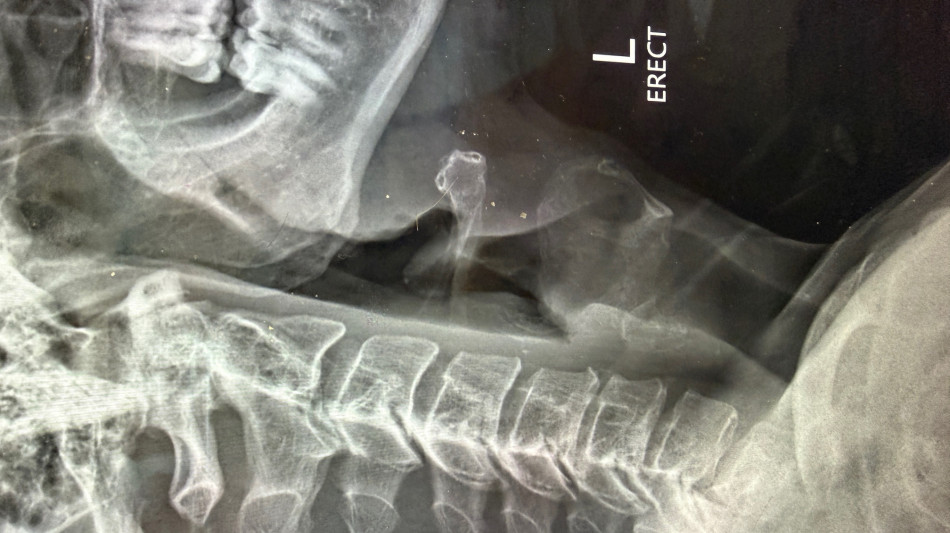

The patient, a 47-year-old man, presented with progressive neck pain, arm pain, and weakness in the setting of spinal cord compression and severe nerve root compression with associated bone spur formation. After failing conservative management, the patient was taken to surgery for a three-level cervical disc replacement to decompress the spinal cord, relieve nerve compression, and remove osteophytic pathology.